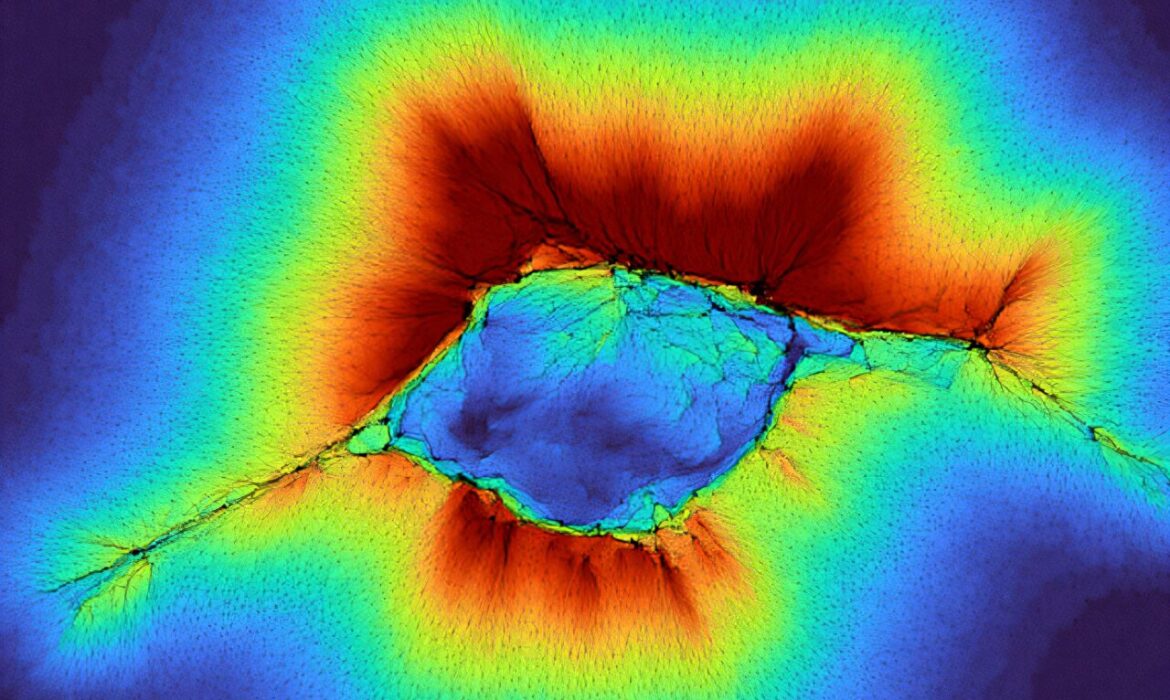

Làm việc cùng nhau, các tế bào có thể cảm nhận vượt khỏi môi trường của mình

Phát hiện mới có những gợi ý về việc phát hiện ung thư.